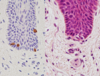

What is shown in the image?

What is the composition of this layer like?

stratum lucidum of the sole of the foot

this consists of several layers of flattened dead cells

nuclei already begin to degenerate in the outer part of the stratum granulosum

in the stratum lucidum, faint nuclear outlines are visible in only a few of the cells